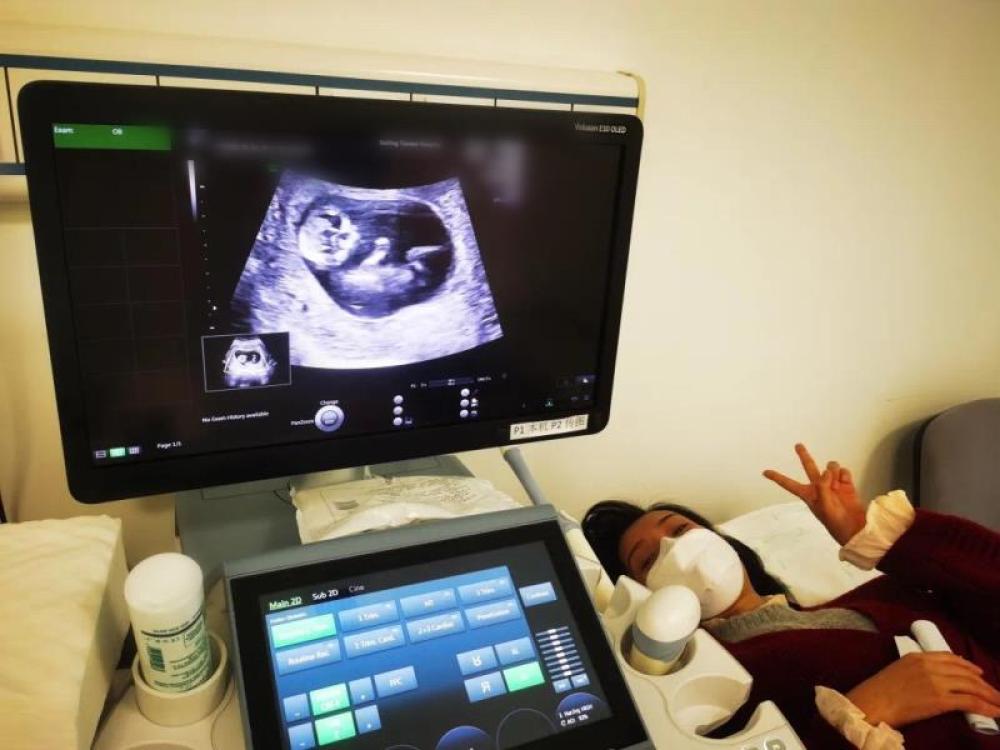

今天一早,妻子去醫(yī)院進(jìn)行B超檢查,同事用手機(jī)拍攝下了B超顯示屏上的畫面,記錄下了這個(gè)87天的小家伙第一次“亮相”。

圖為北京天壇醫(yī)院袁磊愛(ài)人做B超檢查。

“袁磊,看看你們家寶寶,可愛(ài)嗎?”收到同事發(fā)來(lái)的視頻,第一眼就看哭了,身邊的同事看完視頻也哭了。

視頻里,這個(gè)小家伙好像聽(tīng)到了外面的召喚,在媽媽的肚子里伸手、踢腿、翻身,用各種動(dòng)作進(jìn)行回應(yīng)……看到他那小胳膊小腿,一種從未有過(guò)的幸福感不停地向上涌,眼淚怎么也控制不住。

其實(shí)在武漢這么多天,他一直就是我的牽掛,今天終于看到他了,那種感受真是又緊張又激動(dòng),雖然還看不清他的樣子,但是已經(jīng)感受到他的活力。